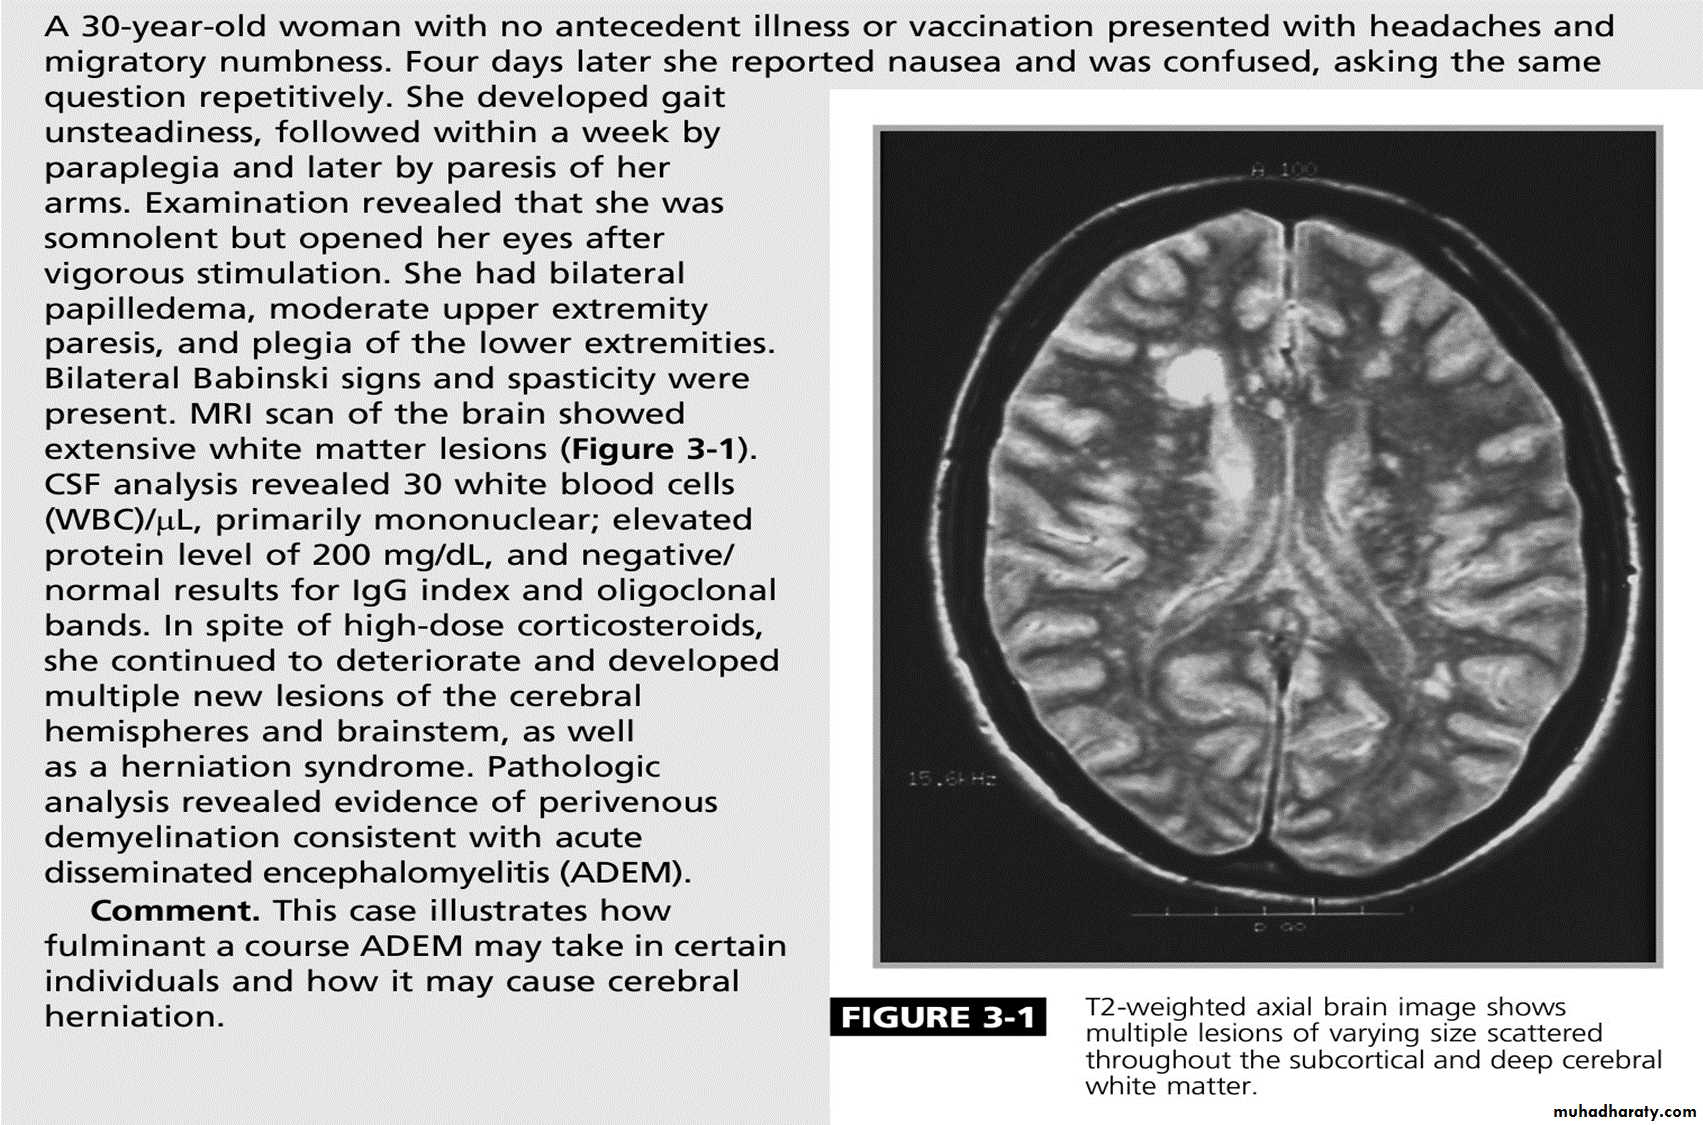

Case

A 42-year-old woman developed progressive bilateral lower extremity numbness and weakness over 5 days, lost the ability to walk, and developed urinary retention. She has also experienced increasingly severe nausea and vomiting over that period. and was found to have an elevated antinuclear antibody during her evaluation for myalgia 3 years ago.Examination shows severe paraparesis, a T9 sensory level, and painful left lower extremity spasms.

A T2-weighted MRI image of her spinal cord shows a lesion extending from T1 to T5 and affecting the central cord. The lesion shows patchy enhancement with gadolinium.

There is increased T2 signal in the area postrema and around the third ventricle.

Acute disseminated encephalomyelitis

This is an acute monophasic demyelinating condition in which there are areas of perivenous demyelination widely disseminated throughout the brain and spinal cord. The illness may apparently arise spontaneously but often occurs a week or so after a viral infection, especially measles and chickenpox, or following vaccination, suggesting that it is immunologically mediated.

Headache, vomiting, pyrexia, confusion and meningism may be presenting features, often with focal or multi focal brain and spinal cord signs. Seizures or coma may occur.

MRI shows multiple high-signal areas in a pattern similar to that of MS, although often with large confluent areas of abnormality. The CSF may be normal or show an increase in protein and lymphocytes (usually 200 cells/L) . The clinical picture may be very similar to a first relapse of MS.Management:

The disease may be fatal in the acute stages but is other wise self-limiting. Treatment with high-dose intra venous methylprednisolone, using the same regimen as for a relapse of MS, is recommended.TRANSVERSE MYELITIS